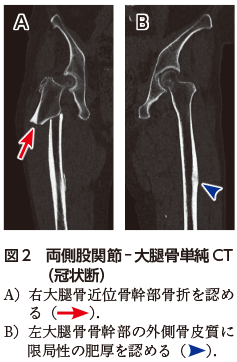

• A1:右大腿骨近位骨幹部に転位を伴う骨折を認める(図1図2A).左大腿骨骨幹部の外側骨皮質に限局性の肥厚を認める(図1図2B).

X線写真において,不全骨折の段階では大腿骨外側皮質にbeakingやflaringと呼ばれる限局性の肥厚を認める.完全骨折では外側骨皮質に端を発した骨を横断する骨折線を認める.ビスホスホネート製剤を長期内服中の患者で疼痛などの前駆症状の訴えがあるが,X線写真で診断がはっきりしない場合は,CT,MRI,骨シンチグラフィでの精査を考慮する.完全骨折を認める場合は外科的な治療を行う.以前は不全骨折に対しても外科治療が選択されていたが,近年ではビスホスホネート製剤を中止し,患肢への荷重を制限することで保存的に治療される.ただし,骨折が進行する場合や持続的な疼痛がある場合には,外科的治療が適応となる.このような治療方針のため,不全骨折の段階で指摘することは,患者のQOLを維持するうえで重要である2).今回の症例のように片側の非定型大腿骨骨折を認める場合は,対側にも非定型大腿骨不全骨折の画像所見がないか,外側骨皮質の肥厚に注意を払うことが大切である1)

図1